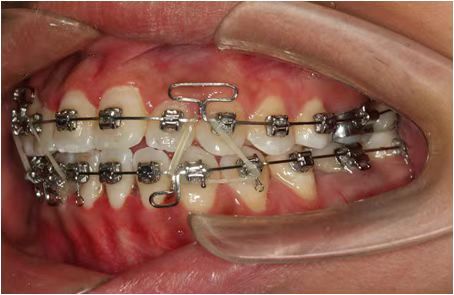

情况:不接受外科手术,在当地做了1年半的矫治,遇到困难无法进行。由外地正畸同行推荐来上海寻求非手术矫治的二手病例。武广增老师接收时的错合畸形情况,呈现严重的骨性反合偏合及侧方开合(图1-图10)。由于推荐其去口腔医院接受正颌外科手术遭到拒绝,武广增老师通过专业的检查、分析,制定一套详细的治疗计划,采用了磨牙推进器技术、武式辅弓技术等特色正畸手段获得明显效果(图2-1~图2-9)。治疗结束后也拍摄了相关照片(图3-1~图3-9)。

2、采用武氏粗丝支抗牵引辅弓,通过颌间个性化弹力牵引纠正右侧侧方开合畸形;️

3、下颌牙弓每側使用方丝三个连续靴形曲和倒置蛤蟆弓技术,与上颌粗丝支抗辅弓之间配置颌间弹力牵引,纠正中线偏斜,以及建立后牙尖窝相嵌紧密咬合关系、前牙覆合覆盖关系。矫治过程中,拔除了下颌2个第三磨牙。

矫治效果

图2-4